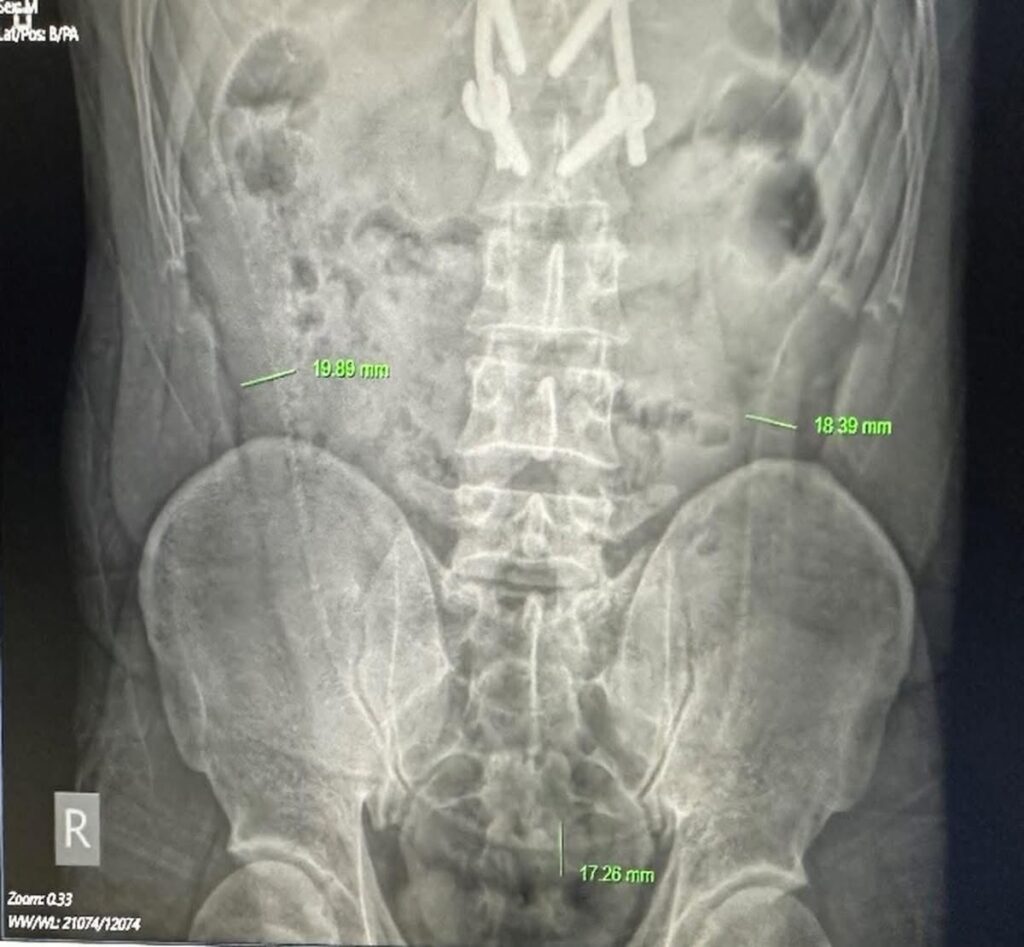

Người bệnh lập tức được thăm khám, chụp film, xét nghiệm, siêu âm. Trên hình ảnh X-quang xuất hiện một “khung xương” cản quang dài nằm trong ổ bụng, vắt ngang ổ bụng từ trái sang phải.